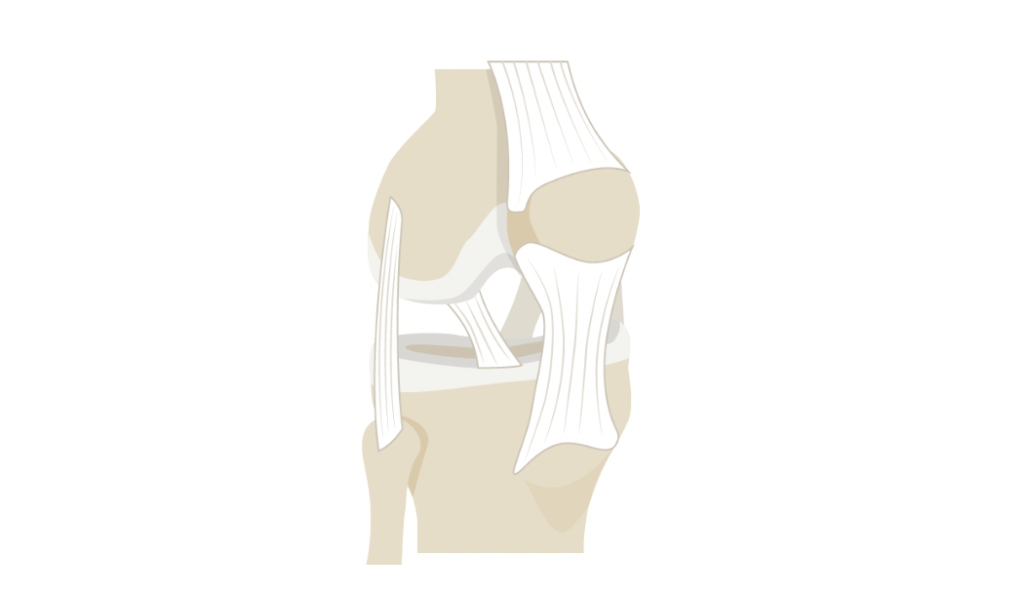

Reconnue pour son efficacité contre les maux du dos, l’ostéopathie est capable de soulager les affections et les troubles du système musculo-squelettique.

Il s’agit des problèmes aigus comme les entorses, les blessures sportives ou chroniques comme les hernies discales, les lombalgies, les douleurs articulaires, les douleurs périnatales, les scolioses et les tendinites. Elle est également efficace contre la fasciste plantaire, le syndrome du canal carpien, l’épine de Lenoir et les troubles musculo-squelettiques (TMS) causés par les postures de travail (travail prolongé à l’ordinateur par exemple).